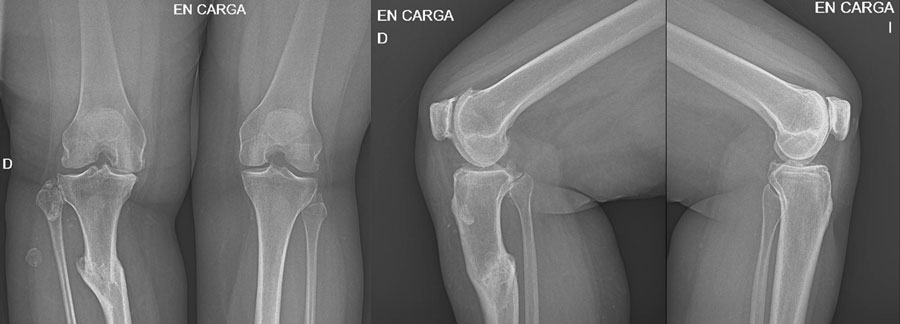

Management of a post-traumatic knee pain: Post-op XRays

Intra-operative images